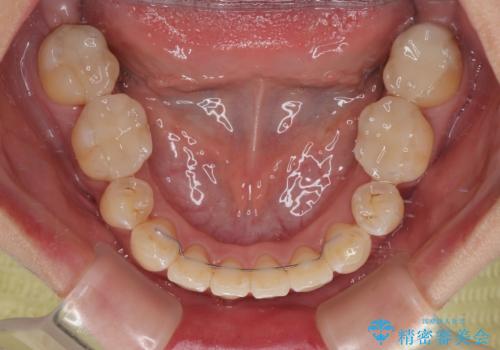

- 前歯1本が後ろ側に隠れてしまうほどのデコボコを気にして来院された患者様です。

前歯のデコボコが顕著なのはもちろんですが、左右ともに奥歯の咬み合わせに問題があり、上顎臼歯が前方位にある状態でした。

上顎は左右の第一小臼歯2本を、下顎は左右第二小臼歯2本を抜歯することで、奥歯の咬み合わせを改善しながら、デコボコを解消していくこととしました。

奥歯の咬み合わせ改善にはどうしても長期間を要します。

3年強とお伝えしておりましたが、予想通り3年3ヶ月で治療を終えることができました。